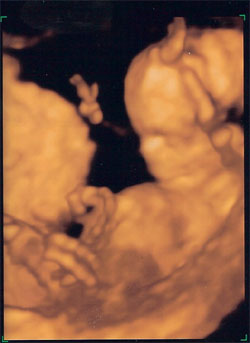

Panka 22 hét 4 naposan. 4D Genesisben készült.

Kép